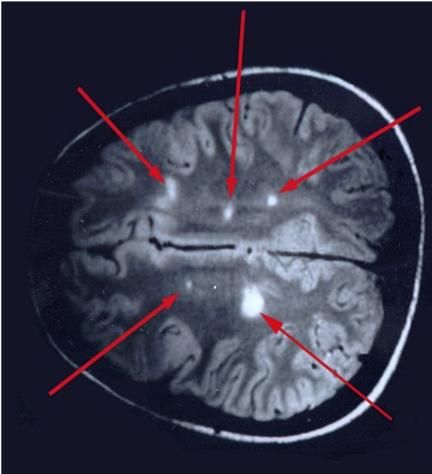

This scan shows what disease

Multiple Sclerosis- scan

What disease is this from

Multiple Sclerosis- stain